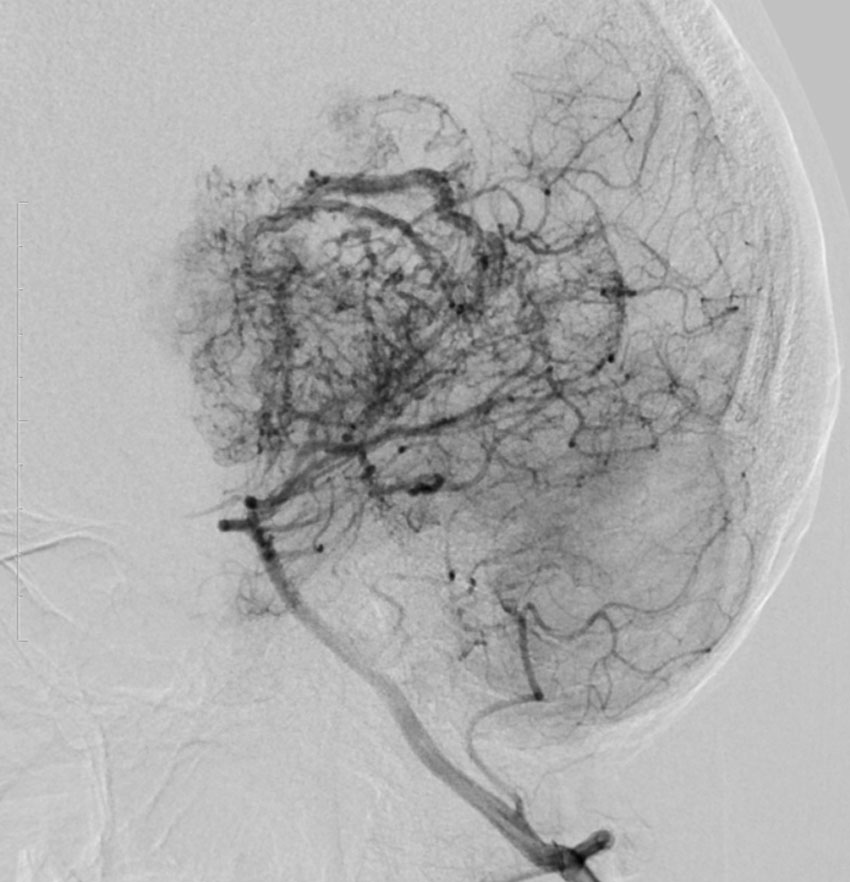

テント上 退形成性上衣腫 グレード3:EPN-ST-RELA negative

膠芽腫を思わせるような,腫瘍内部の壊死,のう胞形成,出血があります。高度の血管増生と動静脈シャントがあり,早期腫瘍静脈描出 early venous fillingがみられます。10代のおそらく右側脳室三角部辺りから発生した退形成性上衣腫です。激しい出血がありましたが全摘出 gross total removal しました。リスクをかえりみない手術も必要です。画像所見も病理組織像も超悪性腫瘍なのですが,治る可能性があるタイプです。